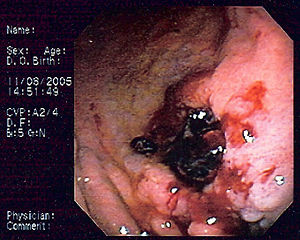

| Endoscopic image of gastric MALT lymphoma taken in body of stomach in patient who presented with upper GI hemorrhage. Appearance is similar to gastric ulcer with adherent clot. | |

MALT lymphoma (MALToma) is a form of lymphoma involving the mucosa-associated lymphoid tissue (MALT), frequently of the stomach, but virtually any mucosal site can be afflicted. It is a cancer originating from B cells in the marginal zone of the MALT, and is also called extranodal marginal zone B cell lymphoma.

The initial diagnosis is made by biopsy of suspicious lesions on esophagogastroduodenoscopy (EGD, upper endoscopy). Simultaneous tests for H. pylori are also done to detect the presence of this microbe.[3]